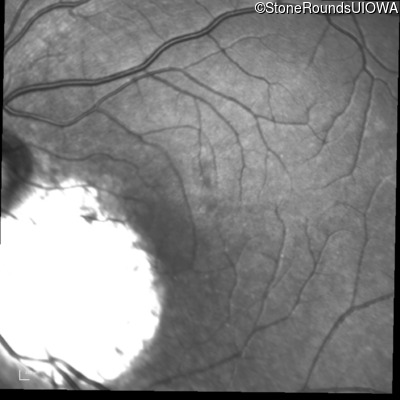

Infrared Fundus Photograph - Left - 20/60 -2 sc

Exemplar